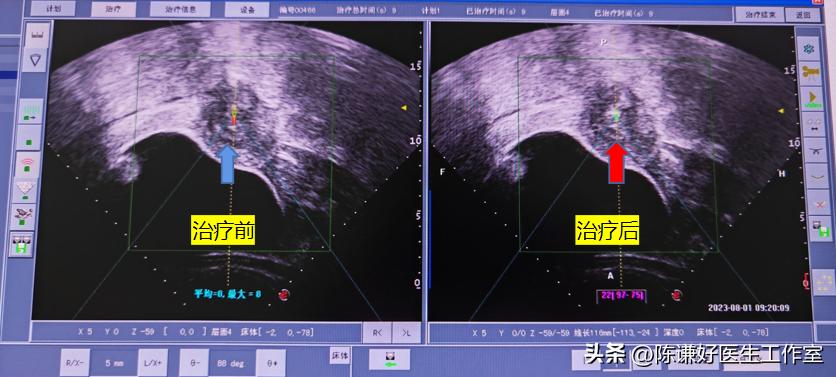

患者昨日在镇静镇痛下进行了海扶刀消融治疗,整个治疗过程中,患者几乎没有特别感觉,术中显示肌瘤坏死超声对比也很明显,术后第二天复查,显示整个肌瘤都已经消融,患者也几乎没有特殊不适,第二天就可以正常出院。

海扶刀治疗中实时超声